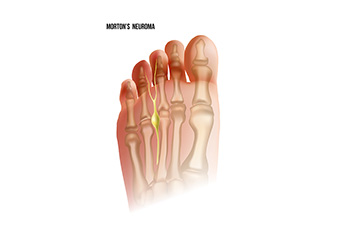

Symptoms and Causes of Morton’s Neuroma

Morton's neuroma is a painful condition that affects the ball of the foot, typically between the 3rd and 4th toes. It occurs when the tissue surrounding a nerve becomes thickened, causing irritation or compression. The exact cause of Morton's neuroma is not always clear, but factors like wearing tight or ill-fitting shoes, particularly high heels, can contribute by putting pressure on the ball of the foot. Other causes include repetitive stress or activities that involve high-impact movements, like running or jumping. Symptoms of Morton's neuroma include sharp, burning pain in the ball of the foot, tingling or numbness in the toes, and a feeling of something being stuck or bunched up in the shoe. These symptoms are often aggravated by walking or standing for long periods. If you have any of these symptoms, it is suggested that you contact a podiatrist who can successfully treat Morton’s neuroma.

Morton’s neuroma is a very uncomfortable condition to live with. If you think you have Morton’s neuroma, contact one of our podiatrists of Crystal Lake Foot & Ankle Center. Our doctors will attend to all of your foot care needs and answer any of your related questions.

Morton’s Neuroma

Morton's neuroma is a painful foot condition that commonly affects the areas between the second and third or third and fourth toe, although other areas of the foot are also susceptible. Morton’s neuroma is caused by an inflamed nerve in the foot that is being squeezed and aggravated by surrounding bones.

What Increases the Chances of Having Morton’s Neuroma?

- Ill-fitting high heels or shoes that add pressure to the toe or foot

- Jogging, running or any sport that involves constant impact to the foot

- Flat feet, bunions, and any other foot deformities

Morton’s neuroma is a very treatable condition. Orthotics and shoe inserts can often be used to alleviate the pain on the forefront of the feet. In more severe cases, corticosteroids can also be prescribed. In order to figure out the best treatment for your neuroma, it’s recommended to seek the care of a podiatrist who can diagnose your condition and provide different treatment options.

Morton's Neuroma

Morton's Neuroma, also called Intermetatarsal Neuroma or Plantar Neuroma, is a condition that affects the nerves of the feet, usually the area between the third and fourth toe. Neuroma refers to a benign growth that can occur in different parts of the body. Morton's Neuroma strictly affects the feet. This condition causes the tissue around the nerves that lead to the toes becoming thick, causing pain in the ball of the foot.

This condition can be caused by injury, pressure or irritation. Normally no lump will be felt, but instead burning pain in the ball of the foot will be experienced. Numbness and tingling may also occur. With the onset of this condition, a person may feel pain when tight or narrow shoes are worn. As the condition worsens, the pain may persist for days, or even weeks.

Persistent foot pain should always be a concern. The foot should be examined by a podiatrist if pain persists longer than a few days with no relief from changing shoes. The earlier the foot is examined and treated, the less chance there will be for surgical treatment.

There are some factors that can play a role in the development of Morton's Neuroma. These include wearing ill-fitting shoes that cause pressure to the toes, such as high heels. Also, high impact exercise may contribute to the cause of this condition. Morton’s Neuroma may also develop if the foot sustains an injury. Another cause includes walking abnormally due to bunions or flat feet. This causes excessive pressure and irritates the tissue. At times, people are affected for no determinable reason.

Podiatrists can alleviate the effects of this condition using a treatment plan to help decrease the pain and heal the foot tissue. Depending upon the severity of the Morton's Neuroma, the treatment plan can vary. For cases that are mild to moderate, treatments may include applying padding to the arch to relieve pressure from the nerve and reduce compression while walking. Ice packs can also help reduce swelling. The podiatrist may also create a custom orthotic device to support the foot and reduce compression and pressure on the affected nerve. The doctor will probably advise against partaking in activities that cause constant pressure on the affected area. They may provide wider shoes to ease the pressure from the toes. If these treatments do not relieve the symptoms of this condition, the doctor may use injection therapy.

Surgical treatment may be recommended by the podiatrist if all other treatments fail to provide relief. Normally, the podiatric surgeon will decide on either a surgical procedure that involves removal of the affected nerve or will choose surgery to release the nerve. After examination, the surgeon will decide on the best approach to treat the problem.

Recovery varies according to the type of surgical procedure. The patient will also be instructed on the best shoe wear to prevent the return of this condition, along with changes to workout routines, if this was a cause. Preventative measures are important in ensuring the condition does not return.